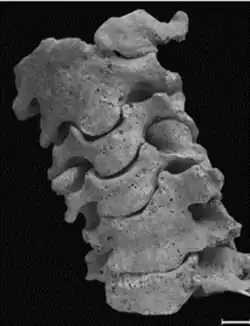

Num segundo caso, descrito por Fernandes e Costa (2007)[4], temos o esqueleto de um individuo de sexo masculino, com cerca de 40 anos de um cemitério medieval em Estremoz, datado do período entre o século XIII e XV. Este individuo tem uma vertebra cervical supranumerária, sendo a C0 uma hemivertebra (lado esquerdo) fundida ao côndilo occipital.

Quanto ao atlas (C1), não está fundido em plano sagital, sendo composto por duas hemivertebras. A hemivertebra direita está fundida com o áxis (C2) enquanto a esquerda não, articulando normalmente (figura 3). Neste par de vertebras a união é completa nos corpos vertebrais e facetas articulares, havendo desenvolvimento de uma ponte óssea entre os arcos. Consequente desta fusão, o áxis apresenta deformações no processo odontóide.

Mais abaixo, a C5 e C6 também estão fundidas (figura 3), tendo uma forma de cunha, que podem sugerir fraturas por compressão (importante no diagnostico diferencial). Aqui existe a união dos corpos vertebrais, e das facetas e arcos direitos, no entanto têm o processo transverso esquerdo independente.

Para alem destas duas fusões, este individuo tem também outras anomalias que estão associadas a um mau desenvolvimento da coluna vertebral. Tem 8 vertebras cervicais, 11 torácicas, 6 lombares e 5 sacrais; uma costela cervical fundida ao processo transverso da C7; fenda no processo espinhoso da T3; leve assimetria na dimensão dos braços; escoliose cervical (figura 3); e diferença na elevação das escapulas (Fernandes e Costa, 2007)[4], que pode sugerir a deformidade de Sprengel. Estas alterações enquadram-se com a síndrome de Klippel-Feil de tipo II.